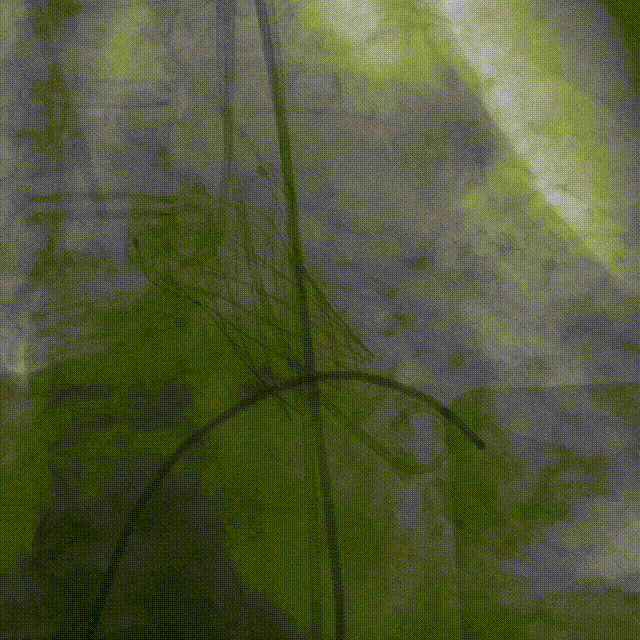

TaurusNXT植入过程

术中影像

TaurusAtlas 18mm球囊预扩张